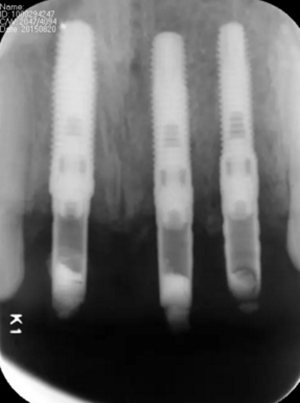

(2)即刻種植、即刻臨時修復(fù)。術(shù)中不翻瓣微創(chuàng)拔除牙根,牙槽 窩骨壁完整。在多級導(dǎo)板輔助下完成種植窩洞制備,植入Bego柱形種植 體,型號分別為:上頜右側(cè)中切牙位點4.1mm×15mm、上頜左側(cè)中切牙 位點?3.75mm×15mm、上頜左側(cè)側(cè)切牙位點3.25mm×15mm,扭矩均為 35N·cm。種植體與唇側(cè)骨壁間隙約2mm,植入Bio-Oss®Collagen骨膠 原。戴入橋用鈦臨時基臺,臨時冠就位順利,自凝樹脂口內(nèi)粘接后適當(dāng)修整 外形,充分磨光,調(diào) 至正中 、前伸 和側(cè)方 與對頜牙均無接觸。術(shù)后 根尖片顯示種植體位置、方向良好。

圖13 術(shù)后即刻根尖片

圖17 術(shù)后6個月根尖片

圖24 最終修復(fù)后即刻根尖片

圖25 最終修復(fù)后復(fù)查口內(nèi)像